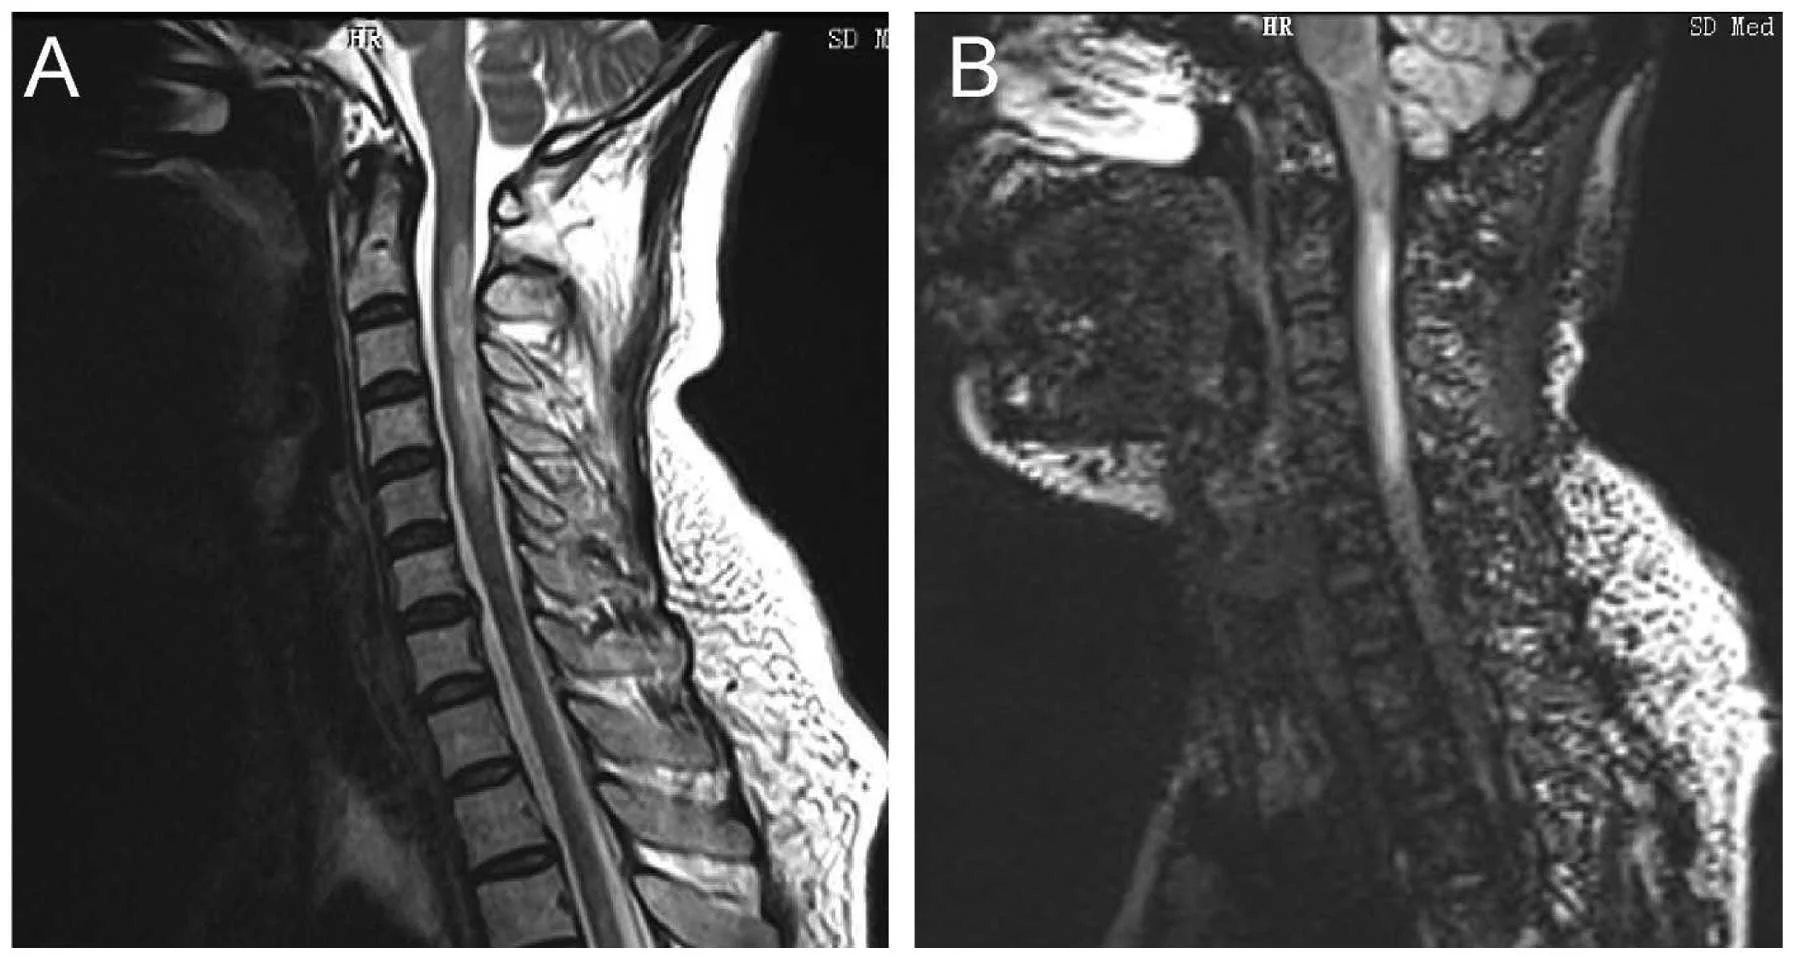

The name explains the areas of the central Nervous System that are commonly affected: the Optic Nerve and the Spinal Cord. Inflammation of the OPTIC Nerves is called OPTIC NEURITIS. Inflammation of the spinal cord is called MYELITIS. Other symptoms include bouts of intractable vomiting and hiccups.